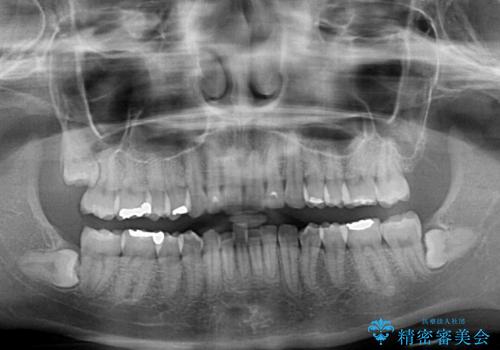

矯正治療の後戻り ガタガタになった前歯の部分矯正

- 以前の矯正治療の後戻りを気にして来院された患者様です。

下顎前歯にデコボコがあるため、ワイヤー矯正により改善することとしました。